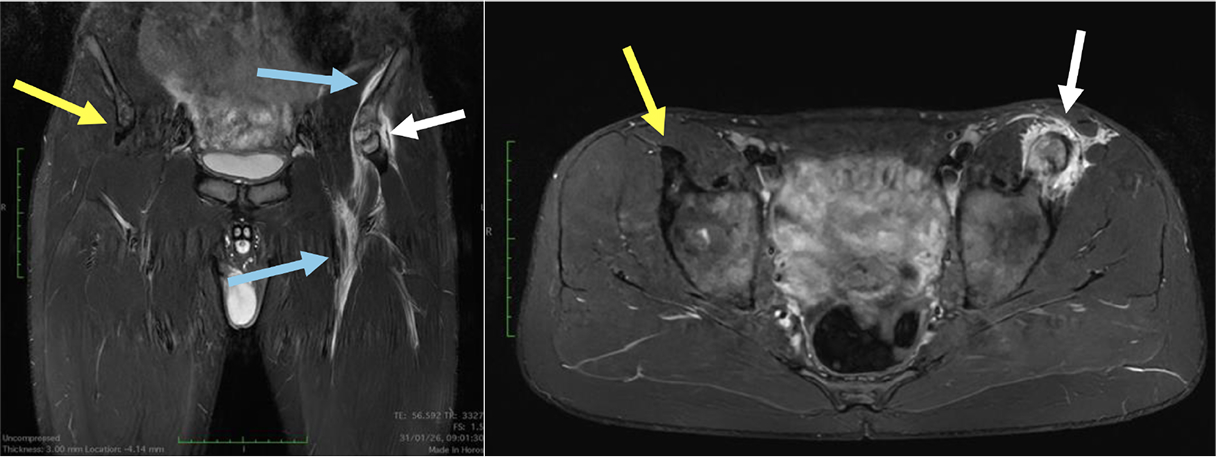

Casi clinici

Scopri come le tecnologie di imaging più innovative di GE HealthCare hanno giocato un ruolo chiave nella diagnosi di condizioni cardiache complesse.